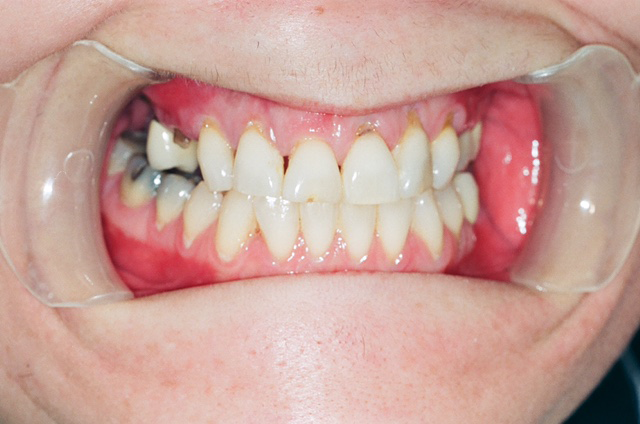

Blackened, rotted, crumbling and broken teeth are just a few of the tell-tale signs that your patient may be using methamphetamine (Fig. 1).

Fig. 1

When they do present to our dental offices, users are often embarrassed by their drug use, concerned about their unattractive smiles and overwhelmed with dental pain. Similarly, as dentists, we may feel overwhelmed by the magnitude and severity of their dental problems and our own uncertainty about which aspects of treatment (surgical, restorative, prosthetic, prevention) to prioritize and initiate.